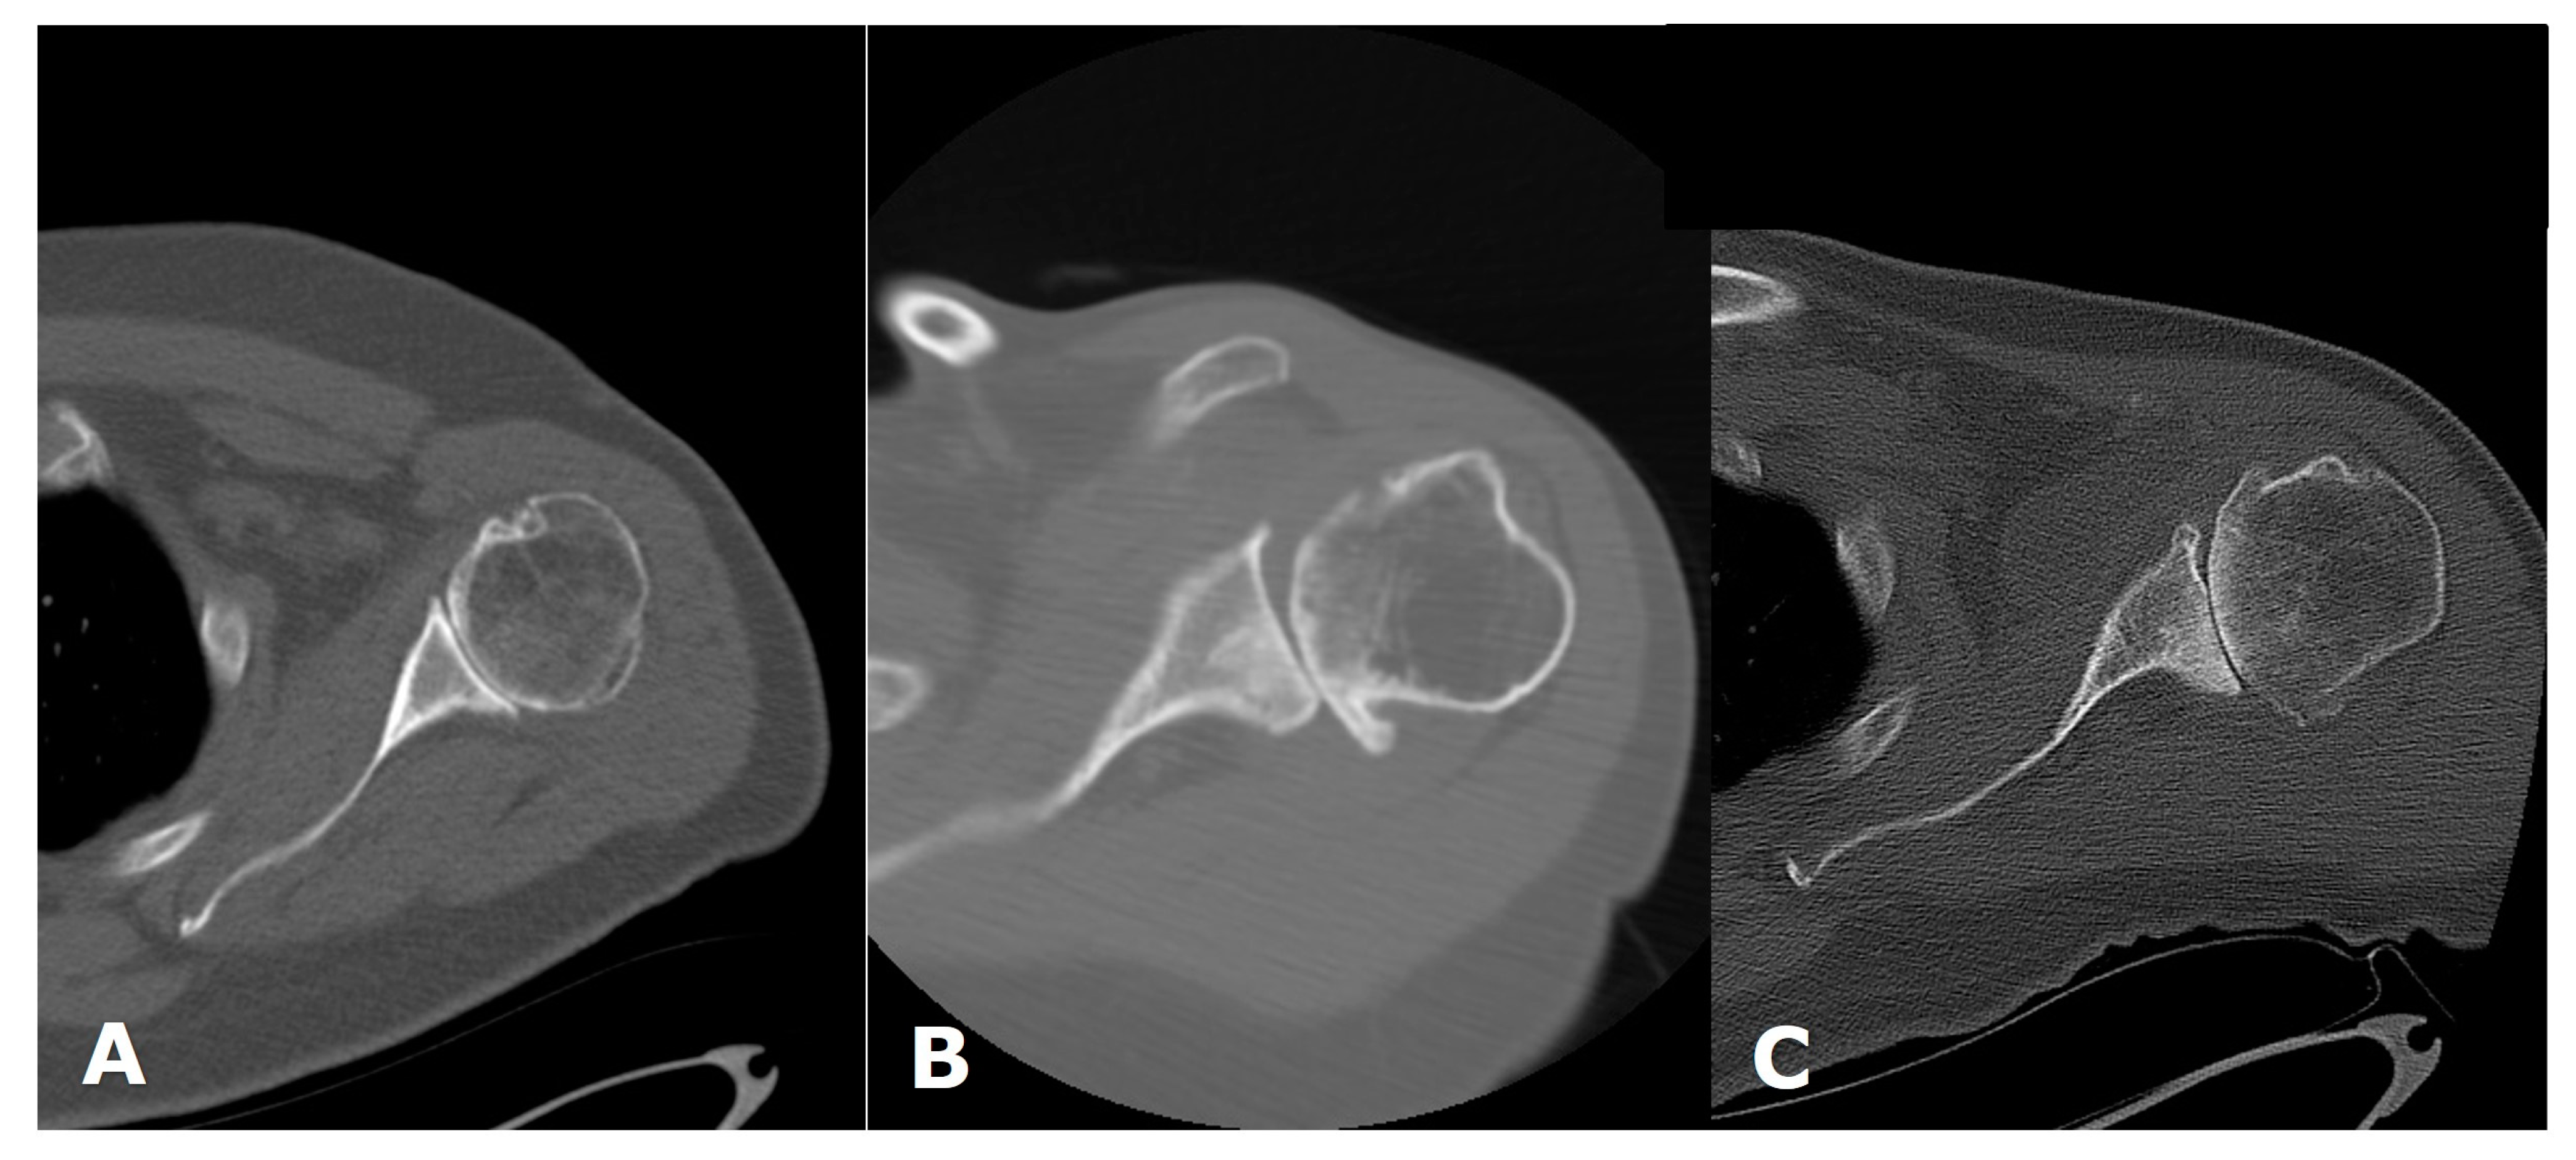

3. Preoperative Imaging

| Type | Description |

| A1 | Mild central glenoid erosion with the humeral head centrally positioned. |

| A2 | Major central glenoid erosion with the humeral head centrally positioned; a line that connects the native anterior and posterior glenoid rims transects the humeral head. |

| B1 | No glenoid erosion; posteriorly subluxed humeral head with posterior joint space narrowing and osteophytes. |

| B2 | Biconcave glenoid due to posterior erosion and retroversion, with posteriorly subluxed humeral head. |

| B3 | Monoconcave glenoid with significant posterior glenoid wear with retroversion of at least 15 degrees or subluxation of 70% or both. |

| C | Retroverted glenoid with glenoid dysplasia. |

| D | Anteverted glenoid or anteriorly subluxed humeral head. |